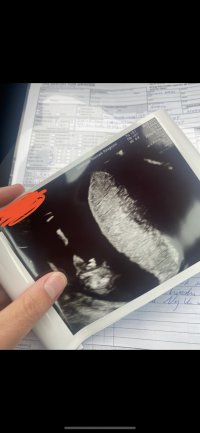

Det var i slik vinkel som bilde nr 2 her at min GY også gjetta på jente 12+3Synes ikke så godt her.. målt til 12+2 men gyn hadde en anelse ved bilde 2 der![]()

hu såg aldri etter "nub".